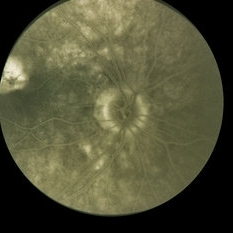

OD with peripapillary scaring.